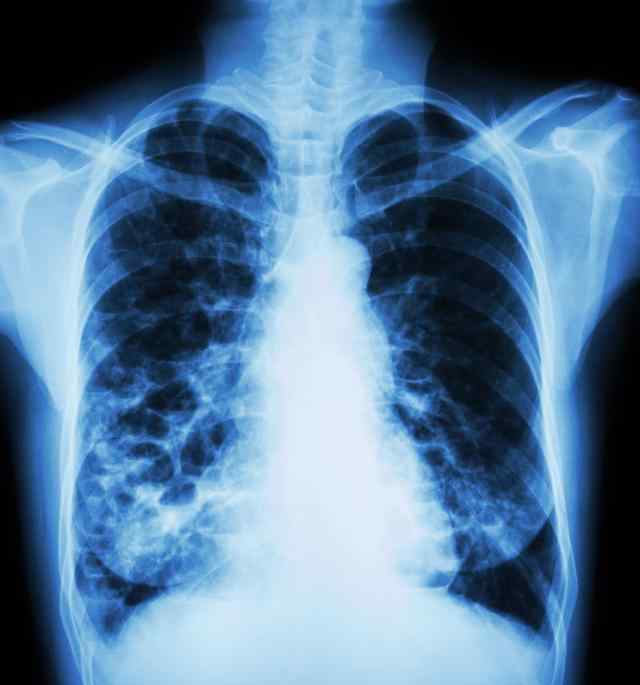

支气管扩张的主要原因是支气管肺组织感染和支气管阻塞。感染引起管腔粘膜充血水肿,使管腔变窄,容易堵塞管腔,导致引流不畅,加重感染;支气管阻塞、引流不畅可诱发肺部感染。因此,它们相互影响,促进支气管扩张的发生和发展。

麻疹、百日咳、支气管肺炎和其他婴儿感染是支气管-肺组织感染和阻塞引起的支气管扩张的最常见原因。由于婴幼儿支气管壁较弱,管腔狭窄,容易堵塞,反复感染破坏支气管壁组织,或细支气管周围组织纤维化,牵拉管壁,导致支气管变形扩张。病变常有两根下支气管,左侧更明显。

支气管扩张可由肺结核纤维组织增生和收缩引起,也可由支气管结核引起管腔狭窄和阻塞引起,伴有或不伴有肺不张,最常见的部位在上叶尖后段或下叶后段。

肿瘤、吸入异物或由管外肿大淋巴结压迫引起的支气管阻塞可导致远端支气管-肺组织感染。支气管阻塞引起肺不张,失去肺泡弹性组织的缓冲,使胸腔内的负压直接拉动支气管壁,引起支气管扩张。右肺中叶支气管细长,周围有多簇淋巴结。非特异性或结核性淋巴结炎常使支气管扩大和压缩,引起肺不张,并发支气管扩张引起的中叶综合征。